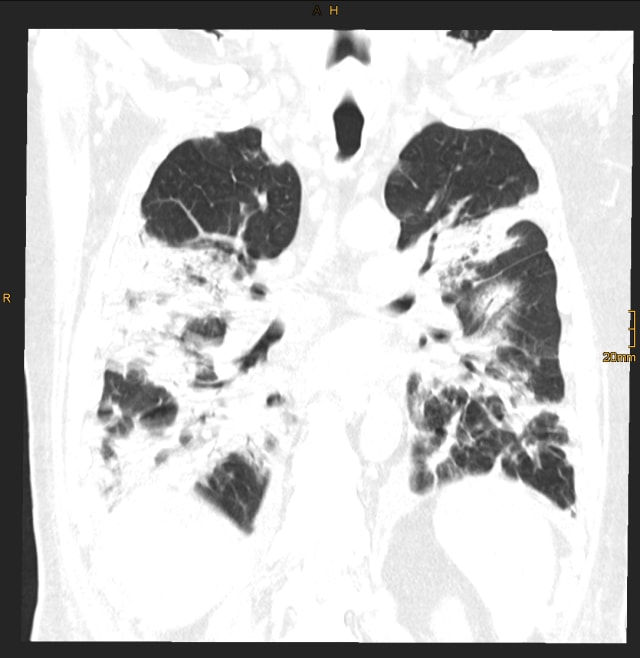

Insgesamt wurden vier CT-Verlaufskontrollen der Lunge durchgeführt, von anfangs 142 Probandinnen und Probanden wurden nach einem Jahr noch 91 Teilnehmerinnen und Teilnehmer in die Studie eingeschlossen (siehe CTs am Ende des Textes).

CT Thorax im Vergleich:

(Sie können das Bild mit dem weissen Pfeil in der Mitte wechseln)

CT Thorax eines Teilnehmers während des stationären Aufenthalts. | Univ.-Klinik für Radiologie Innsbruck